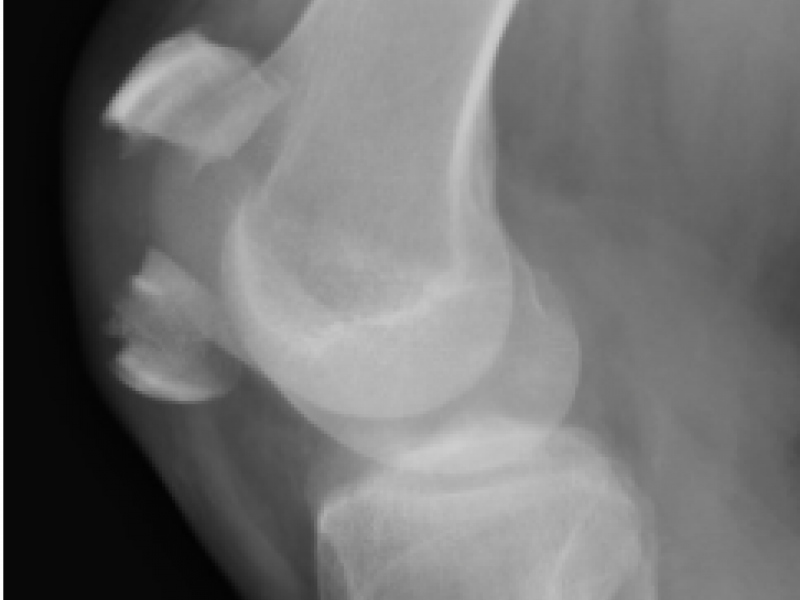

What's the Diagnosis? By Dr. Eric Chavis

A 50 yo M with no PMHx presents to the ED with knee pain